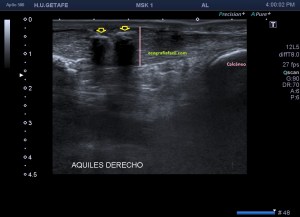

Normalidad, en la imagen 1 y 2 ves un aquiles normal.

Las imágenes 1 y 2 son la normalidad, es lo que casi nunca solemos ver en este tipo de estudios, pero en ocasiones sí, y como además cuando realizamos este protocolo, siempre es recomendable explorar lado contralateral, podemos muchas veces comparar la región patológica con la normal. El aquiles lo estudiamos siempre en toda su longitud, desde la inserción hasta su origen, en eje corto y en eje largo. Fijándonos bien en toda la ecoestructura posterior de la pierna y estudiando la profundidad de la grasa de Kager.

Las fibras del tendón son alargadas, lineales, tensas con las flexión dorsal.

Ojo con la anisotropía, la hipoecogenicidad producida el ligero cambio de angulación del tendón cuando inserta en el calcáneo posterior…La clave, hiperflexión dorsal, mucho gel y amoldar la posición de la sonda para estudiar estas fibras insercionales.